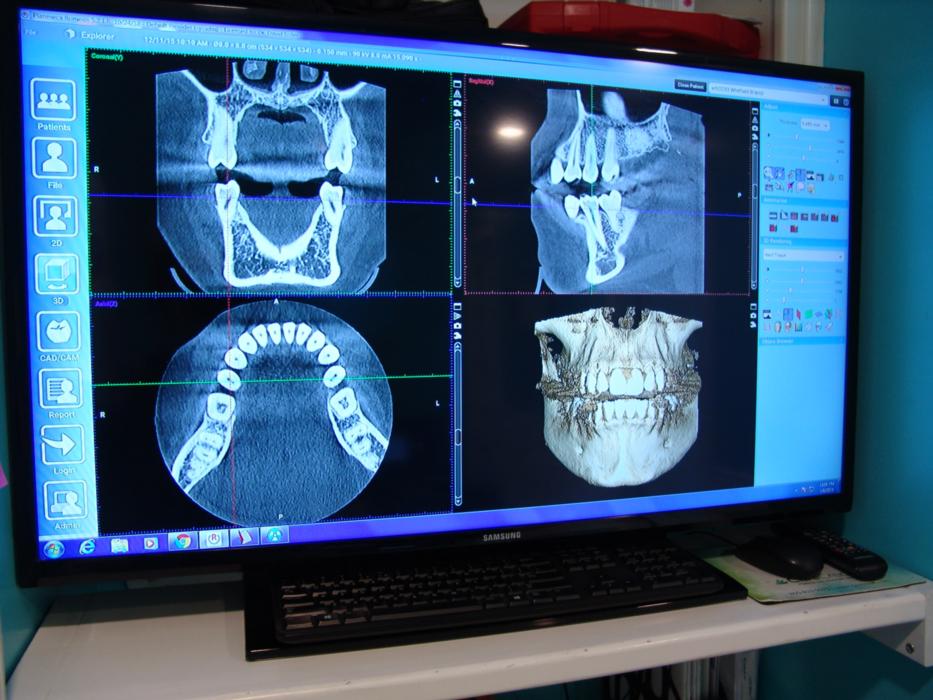

- Cone Beam Computed Tomography (CBCT): CBCT provides a three-dimensional view of the teeth, bone, nerves, and soft tissues in the mouth. It is often used for more complex treatments like dental implants and orthodontics.

This allows us to see your teeth and jaw in cross-sections which enables us to identify infections and abnormalities that can not be seen on conventional X-Rays.